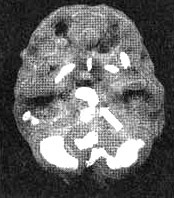

Мозг Ли Анн — депрессия

Иллюстрация к книге — Измените свой мозг - изменится и жизнь! [i_032.jpg]

Трехмерное изображение снизу — активный мозг. Обратите внимание на повышенную активность в лимбической системе.